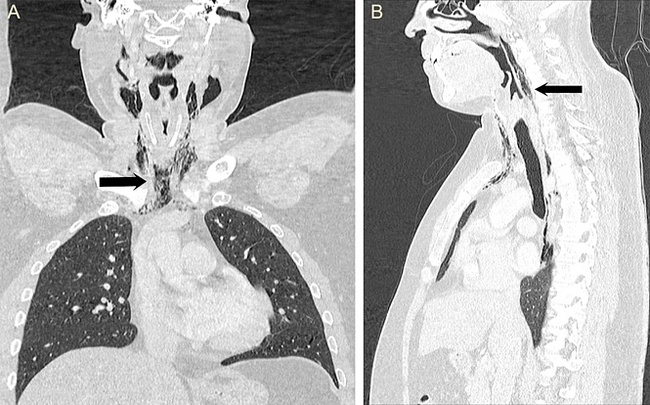

Компьютерная томография шеи (B) и грудной клетки (A).

На шее стрелкой показана эмфизема, в грудной клетке возле позвонка T9 — эмфизема средостения Опасаясь, что у чихуна разовьется инфекция или в грудной полости зародятся воспаления, медики оставили его в лечебнице, долгие дни пичкали антибиотиками и кормили через трубку, засунутую в носоглотку и ведущую в желудок. Бр-р-р, короче. На больничном режиме страдалец пробыл несколько недель, потом еще пару месяцев за ним вели пристальное наблюдение, не случатся ли рецидивы. Но, к счастью, обошлось.